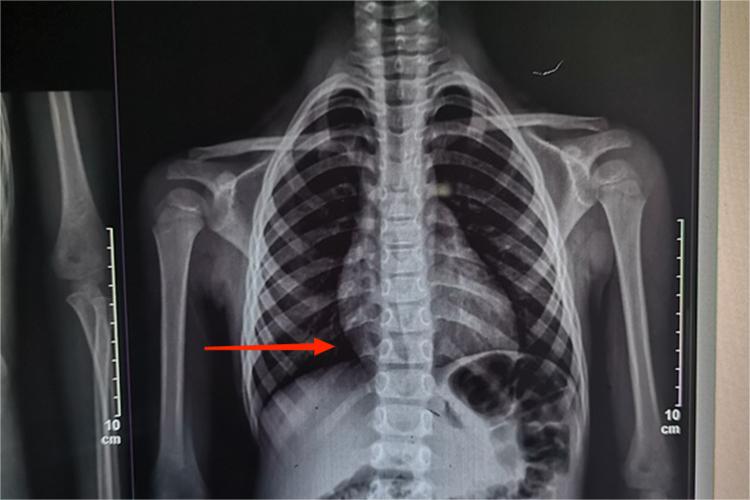

轻度脊柱侧弯是指20度以内的脊柱侧弯,可表现为双肩不等高、胸廓不对称。

轻度脊柱侧弯临床表现为脊柱的一个或多个节段,在冠状面上偏离身体中线,而向侧方弯曲,形成带弧度的脊柱。一般从外观上没有明显的躯体畸形,患者也无自觉症状,多是在体检时发现,部分情况下也可表现为身高不及同龄人、双肩不等高、胸廓不对称等情况。